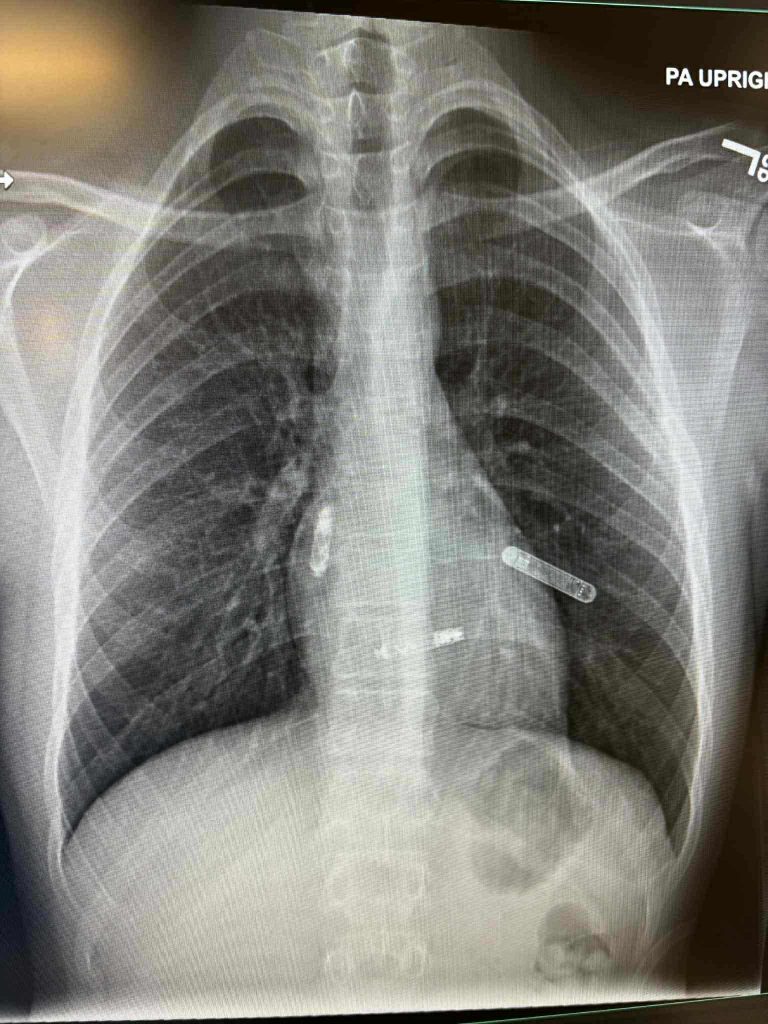

Ova izuzetna ljekarka uspješno je pacijentu ugradila dvokomorni pejsmejker direktno u srčane šupljine — u pretkomoru i komoru — čime je postignuta potpuna sinhronizacija i pravilniji rad srca. Ono što ovaj zahvat čini posebnim jeste činjenica da je ovo prva takva operacija izvedena na Floridi, a stručnjaci je nazivaju velikim iskorakom u liječenju srčanih oboljenja.

Za razliku od tradicionalnih pejsmejkera, koji se postavljaju ispod kože i povezuju žicama koje prolaze kroz vene, nova tehnologija omogućava direktnu ugradnju uređaja unutar srca, bez žica. Ovim pristupom smanjuje se rizik od komplikacija i povećava efikasnost rada srca.

“Dvokomorni pejsmejker sinhronizuje rad pretkomora i komora, što znači pravilniji ritam i bolju pumpnu funkciju. Ovo je ogroman napredak za pacijente s poremećajem srčanog ritma,” navodi se u objavi.